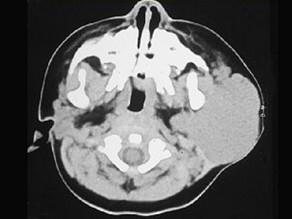

问题 1岁女孩,左耳垂下进行性增大肿块3个月,触之质软,下面是其颈部CT检查结果,其中左图是普通扫描,右图是增强扫描。请问,患者最可能的诊断是 ( )

选项 A、腮腺淋巴结结核 B、腮腺黏液表皮样癌 C、腮腺腺样囊性癌 D、腮腺血管瘤 E、腮腺混合瘤

答案 D